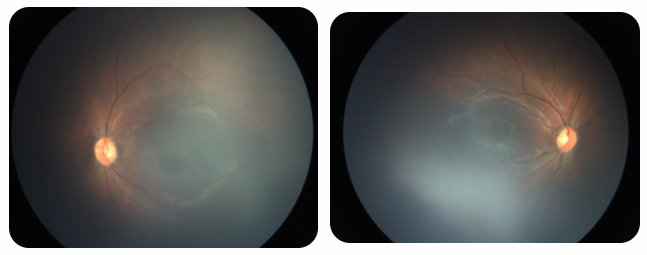

廈門眼科中心黎曉新名醫(yī)工作室曾接診一名31周出生的早產(chǎn)兒,出生體重僅1300克。由于家長缺乏篩查意識,直到孩子5個月大時眼睛仍不會追光,才前來就診。檢查發(fā)現(xiàn),患兒ROP已進(jìn)展至4B期,因纖維血管增殖牽拉導(dǎo)致視網(wǎng)膜脫離,錯過了最佳治療窗口。盡管黎曉新教授團(tuán)隊成功實施了玻璃體切割手術(shù),孩子的視力仍存在不可逆損傷。此后,孩子開啟了長期隨診復(fù)查、治療的“護(hù)眼征程”,目前其右眼矯正視力為0.6,左眼為0.8。

近期術(shù)前檢查:

早產(chǎn)兒視網(wǎng)膜病變

術(shù)后復(fù)查:

相比之下,另一位早產(chǎn)寶寶在出生5周后,生命體征穩(wěn)定之時,便在產(chǎn)科醫(yī)生的建議下轉(zhuǎn)診至廈門眼科中心。經(jīng)篩查確診為Ⅲ期ROP,黎曉新教授團(tuán)隊及時為其進(jìn)行了激光治療。半年后復(fù)查顯示,寶寶的視網(wǎng)膜血管發(fā)育正常,視力發(fā)育與足月兒童無異。